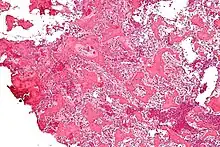

Histological findings

On histological examination, osteoid osteoma consists of a small (< 1.5–2 cm), yellowish-to-red nidus of osteoid and woven bone with interconnected trabeculae, and a background and rim of highly vascularized, fibrous connective tissue. Varying degrees of sclerotic bone reaction may surround the lesion. Benign osteoblastoma is virtually indistinguishable from osteoid osteoma. The usual appearance included a fibrovascular stroma with numerous osteoblasts, osteoid tissue, well-formed woven bone, and giant cells. The osteoblasts were generally small and regular in shape.[7]